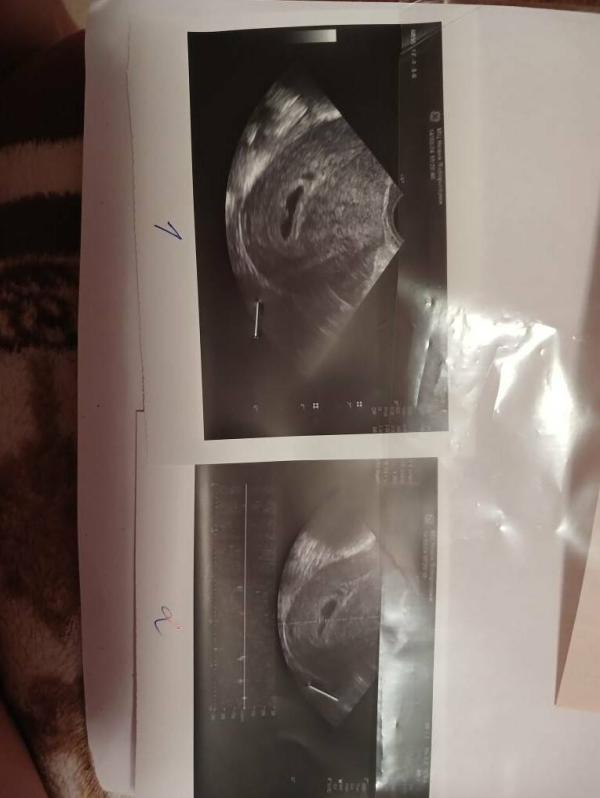

Один плод на УЗИ, но форма вытянутая: что это может быть?

Вопросик, сходила на УЗИ, врач сказала что плод один, но ей не понравилось что вместо горошины вытянутое, и тут мне сказали,а не может это быть двойней? На прием только во вторник, а мысль эта не дает покоя сейчас